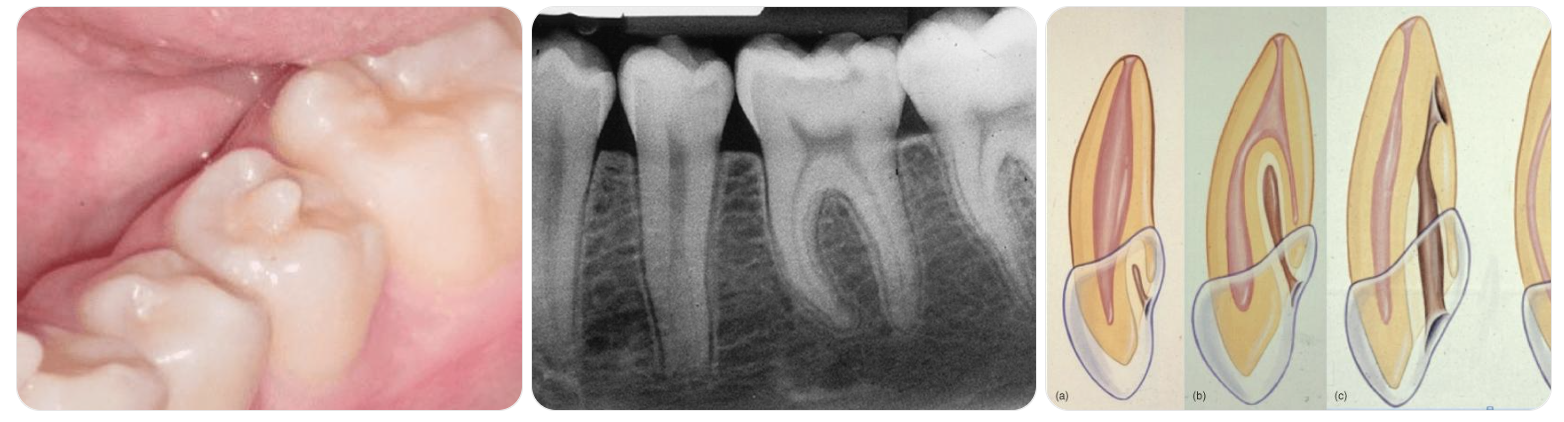

Phân loại dựa trên tình trạng tủy và mức độ phát triển chân răng:

6 nhóm lâm sàng điển hình

Đây là phân loại quan trọng giúp bác sĩ lựa chọn đúng phác đồ điều trị và tiên lượng.